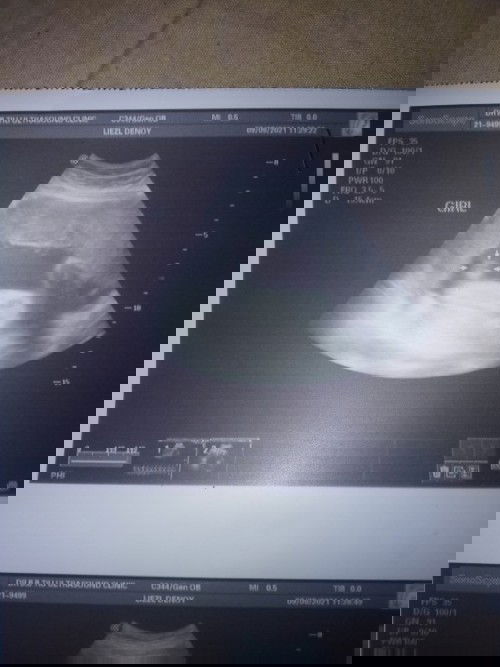

hello po mga mommies ok lang po ba result nang pelvic ultz ko??